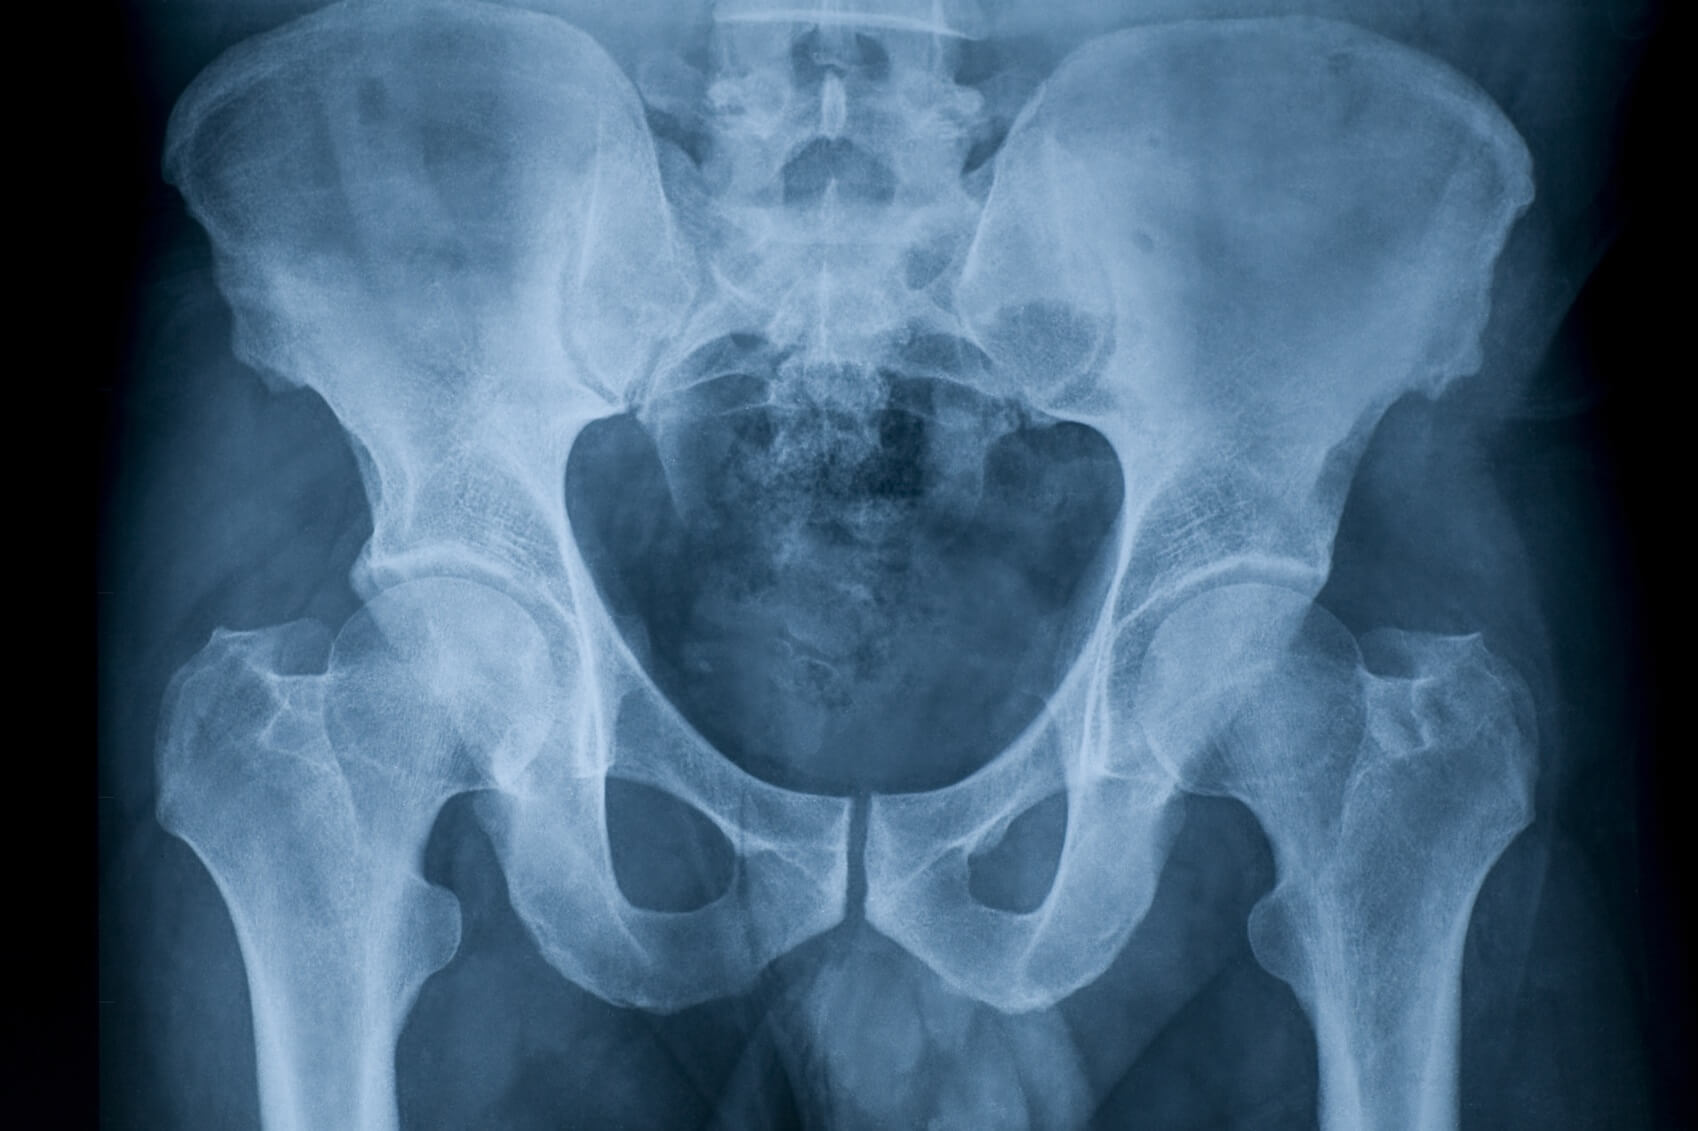

- рентгенографическое исследование – его привлекают в первую очередь. Но рентгенография позволяет выявить уже сформировавшееся суставное тело. Если же некротический процесс только начинается, то пораженный участок хрящевой ткани выявить не удается. Поэтому если наблюдается блокировка сустава, но на рентгенограмме нет изменений, свидетельствующих о наличии патологии, это не исключает развития рассекающего остеохондрита тазобедренного сустава. В таких случаях рекомендуется проведение более информативного метода исследования;

- компьютерная томография (КТ) – с помощью компьютерных срезов можно выявить некротический очаг, который предшествует формированию суставного тела;

- магнитно-резонансная томография (МРТ) – как и КТ, помогает исследовать глубокие слои тканей на предмет начинающегося некроза;